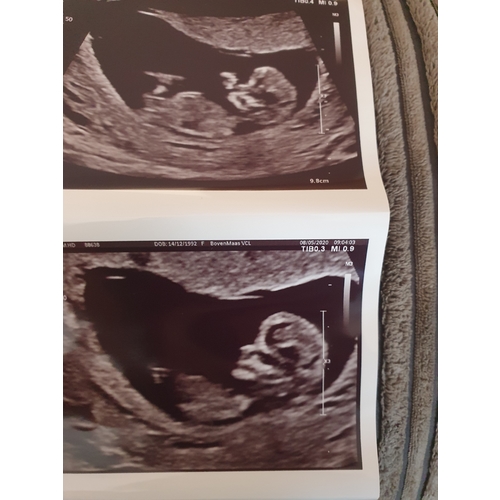

Wat denken jullie meisje of een jongetje.. spannend!

Jongen denk ik, ook de nub馃挋

Wat denk je van mijne ?